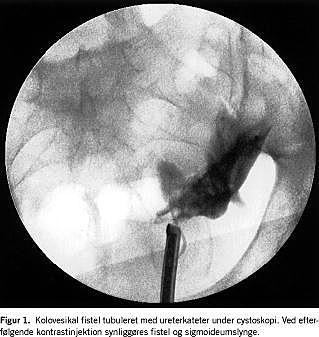

I. En 27-årig kvinde fik recidiverende urinvejsinfektioner og pneumaturi. En cystoskopi viste fistelåbning højt på blærens bagvæg. Ved kontrastinjektion via et ureterkateter i fistelåbningen kunne man se fistelgangen og en colonslynge (Figur 1). En computertomografi (CT) viste luft i blæren og vægfortykkelse af colonslyngen i tæt relation til blærens venstre side. Ved en sigmoideoskopi fandt man en kort koncentrisk benign udseende striktur. Der blev udført laparoskopisk sigmoideumresektion. Man fandt sigmoideum adhærent til venstre blærehjørne. Der kunne ikke findes en fistelåbning i blæren, og ved en efterfølgende fyldning af blæren med metylenblåt kunne der ikke påvises lækage. Der blev ikke foretaget suturering af blæren. Tarmen blev delt distalt og trukket frem gennem Phannenstiels incision, reseceret og anastomoseret med cirkulær stabler. Operationen tog 280 minutter. Patienten blev udskrevet efter fire dage og havde et komplikationsfrit efterforløb. Histologien var forenelig med morbus Crohn.